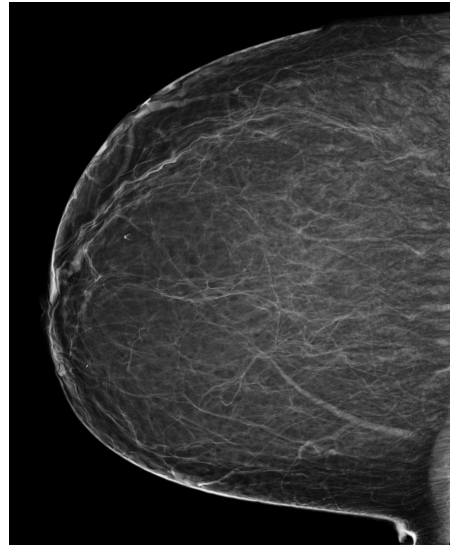

Refer to caption

(a) FeatAlign

(b) FeatAlignReg

(c) ImgFeatAlign/ImgAlign

(d) FeatAlign

(e) FeatAlignReg